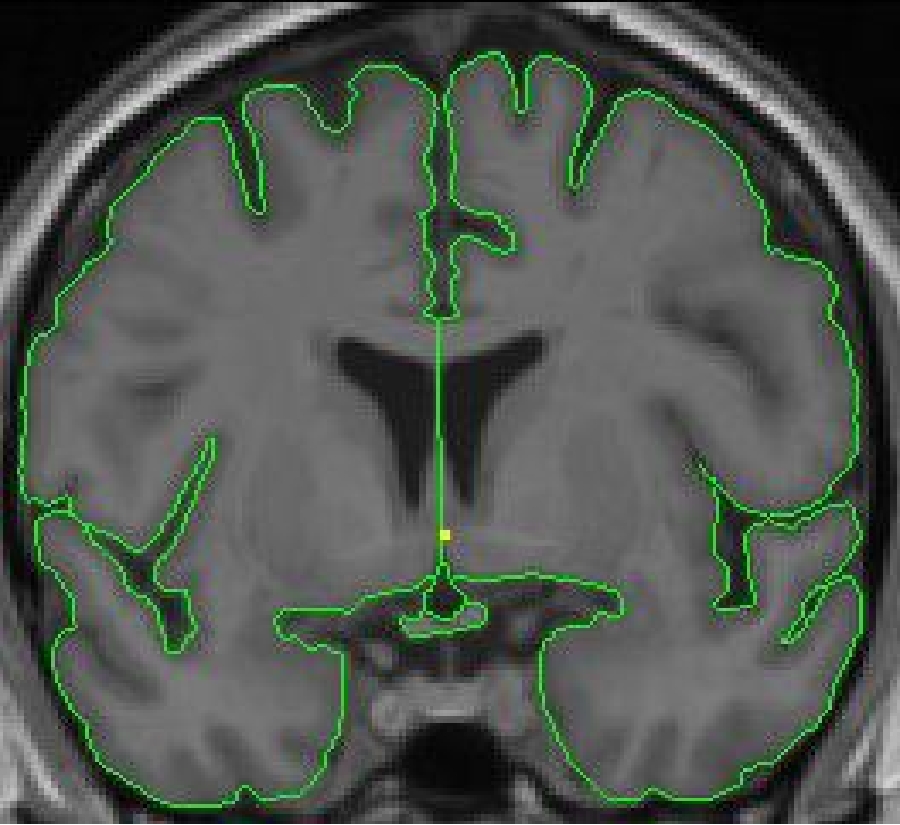

The outline for the optic chiasm is created using the intensity contour function ( press c) and manual drawing. Start segmenting the optic chiasm, from anterior to posterior, on the first slice it becomes the inferior border of the third ventricle. This is in the proximity of the coronal slice containing the anterior commissure.